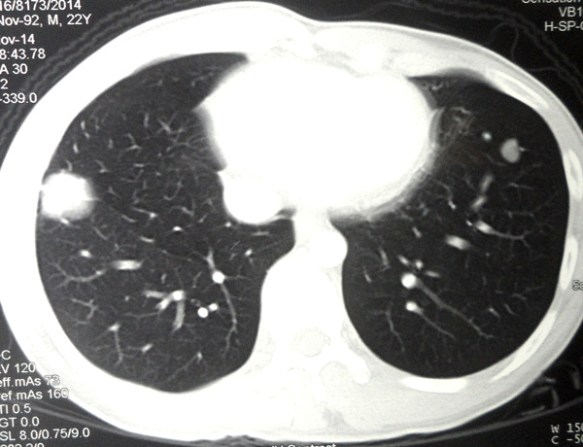

Lung Cancer: After Surgery, Chemo and Radiation, the cancer spread to his healthy lung

CK is a 62-year-old male from Kuala Lumpur. He and his wife came to see us with copies of his medical reports neatly filed in a folder. This is a very pleasant couple who is now helpless and directionless. This is what happened.

1)  20 December 2015: Had food poisoning after taking expired red wine.

2)  21 December 2015: Consulted a GP who discovered “cracking sound” in his left lung.

3) 22 December 2015: CT scan of chest showed a 3.2 x 5 cm mass in the left lung.

4)  2 January 2016: A CT-guided biopsy confirmed a bronchoalveolar adenocarcinoma.

CK was referred to a cardio-thoracic surgeon in a “heart hospital.”

5)  14 January 2016: PET scan confirmed carcinoma of the left lung with no associated locoregional or distant metastasis.

6)  23 January 2016: Admitted to the “heart hospital” for lower lobe lobectomy, i.e. surgery to remove a quarter of the lung.

The surgery was a “success” and histopathology report showed:

1. a) Aortic wall adventitia was infiltrated by tumour.

2. b) One pulmonary lymph node showed tumour metastasis.

3. c) lower lobe of left lung — invasive adenocarcinoma with predominant bronchoalveolar and papillary pattern.

7)  February to June 2016: Underwent 4 cycles of chemotherapy and 20 sessions of radiotherapy.

Things seemed to be okay after all these treatments but CK had chest pains, coughs and fever. He was prescribed “strong” antibiotics.

8) 30 March 2017 — after slightly more than a year.

Follow up CT scan showed multiple nodules and patchy opacities in the upper and lower lobes of right lung.

Radiologist suggested: Differential diagnosis: lung metastases and pneumonia. Suggest close follow up CT lung after a course of antibiotics.

CK went back to his surgeon about this new development. The surgeon was pretty sure that the spots were not cancer related.

9)  1 June 2016:  CT scan of chest. The radiologists wrote the following:

CT on 23 March and 30 March 2017 were reviewed. The current CT is about 2-3 months after  the previous CTs. The current CT showed the following:

1. a) The ground glass opacities in the right upper and lower lobes of the lung appears more dense and larger.

2. b) Newer small nodular lesions are seen in the right upper and lower lobes.

Based on the above observations, the radiologist was of the opinion that this new development was a metastasis or recurrence. However, ground glass opacities may  be due to drug induced lung changes and infection.

The changes in the left upper lobe (note: left lower lobe was removed) are suggestive of non-neoplastic process and fibrosis. If DXT (radiotherapy) was given, these could be due to that treatment.

10) 18 September 2017: Went back to the same GP again (as in 2). “Cracking sound” at the lower part of my good lung.

Cancer marker in December 2016 was 16. In July 2017,it was 173.